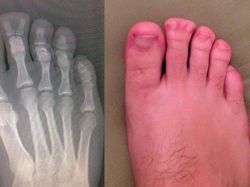

Coba perhatikan bagian telunjuk kakinya. (Foto: Brightside)